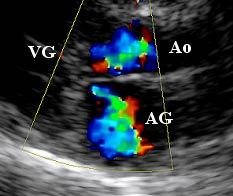

Le cliché ci-contre montre

un exemple d'anomalies

détectées en mode Doppler

couleur (chat atteint de CMH

obstructive) : la tâche en

couleur en haut de l'image

correspond aux turbulences

du sang traversant la région

sous-aortique rétrécie.

La deuxième, en dessous, correspond à la visualisation du sang refluant

du ventricule gauche dans

l'oreillette gauche (fuite

mitrale).

(Source : Cliché PR. V.

Chetboul, Unité de

Cardiologie d'Alfort) |